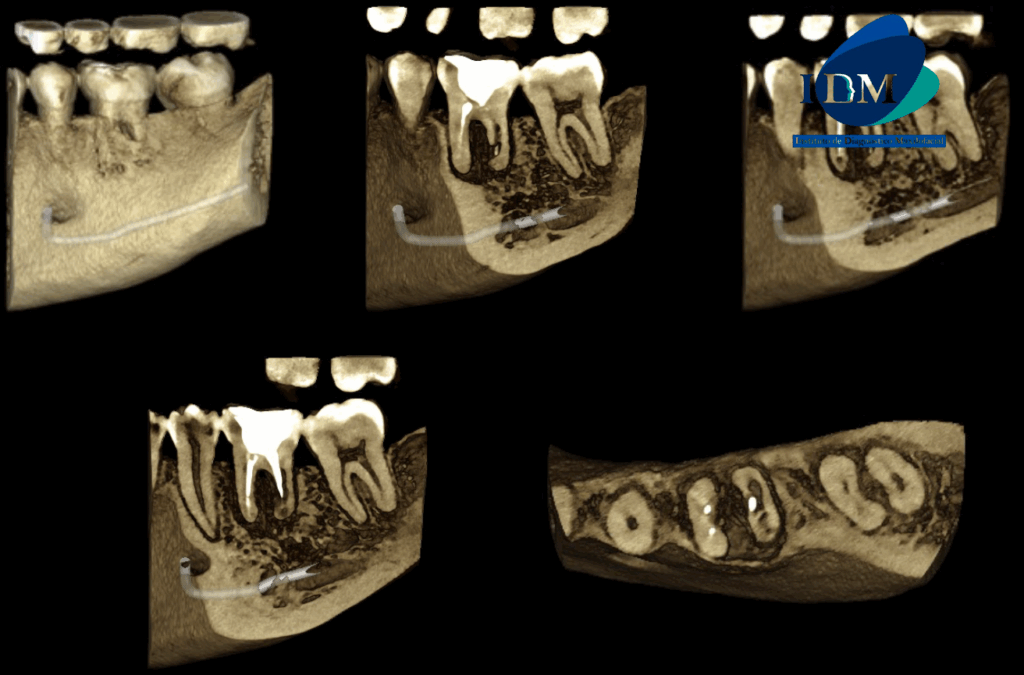

A la evaluación de la tomografía computarizada se puede observar el tratamiento de conductos de ambas raíces, sim embargo el conducto distal presenta una obturación orientada hacia la superficie interna a nivel de tercio medio radicular (vista en cortes axiales), asimismo observamos en cortes tangenciales la reabsorción radicular externa de la raíz distal que compromete el tercio medio y apical. La raíz mesial presenta reabsorción radicular externa de tercio apical. Finalmente se evidencia compromiso de la tabla ósea lingual (cortes transaxiales) y osteítis condensante circundante.

RECONSTRUCCIÓN 3D